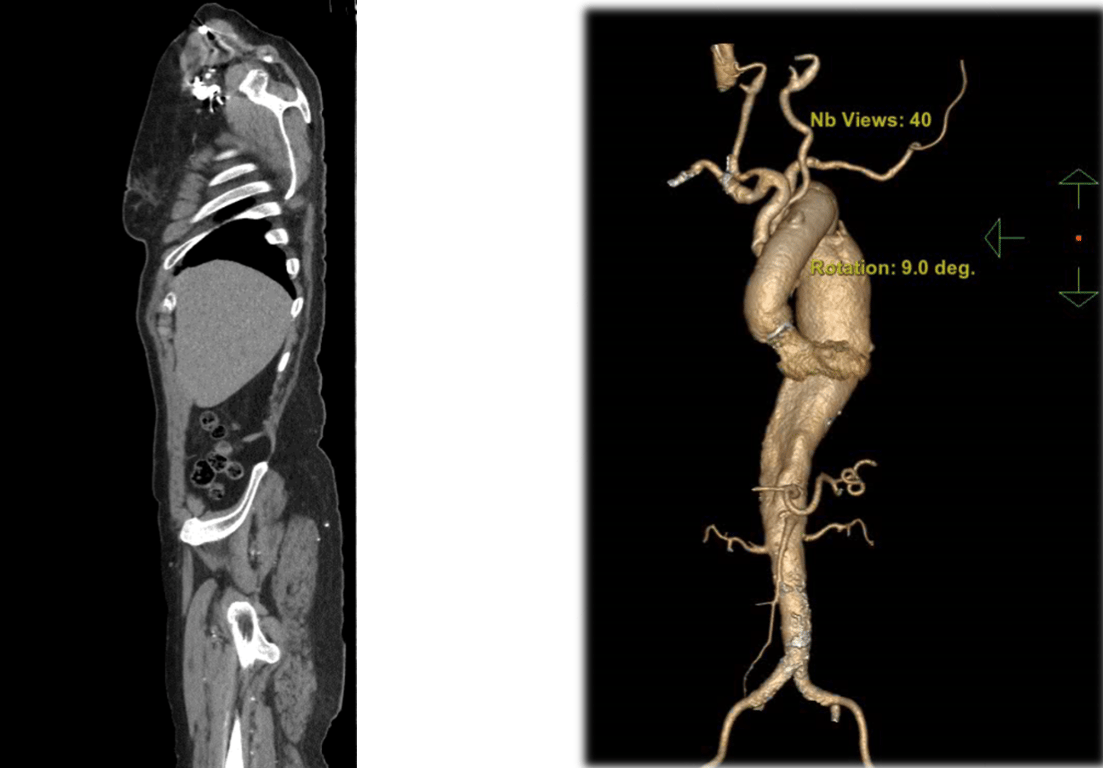

"Аорта — це велика магістральна судина, яка розповсюджує кров із серця по всьому організму. В цієї пацієнтки була уражена аорта на всьому протязі: від аортального клапана до клубових артерій. Це було дуже непросте рішення, тому ще комплексна патологія, і наша задача була зробити так, щоб вона була здоровою", — розповів заступник директора з хігургічної роботи Сергій Варбанець.

Аорта. Фото: пресслужба

За його словами, діаметр аневризми в цієї пацієнтки був майже 7 сантиметрів. Такий діаметр має шанси розриву упродовж року. Варбанець зазначив, що у 30% пацієнтів вся аорта може розірватися і лопнути. Що стосується пацієнтки, то у перспективі року або двох шансів повноцінно жити у неї не було.

Аневризма у пацієнтки. Фото: пресслужба

Першою пацієнткою в Україні, яка перенесла таке важке хірургічне втручання стала 76-річна Віра Сандул. Лікарі поміняли їй аортальний клапан, висхідну аорту, дугу аорти, низхідну грудну аорту та черевну аорту.